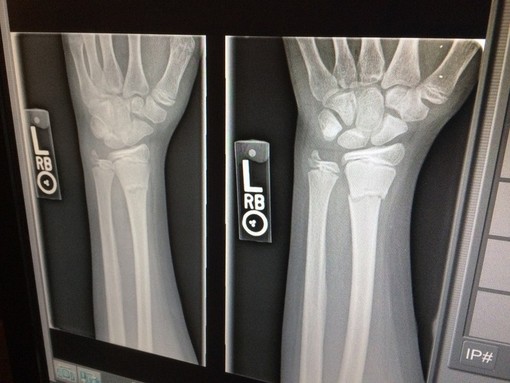

Il trasporto dei pazienti fragili nei servizi radiologici ospedalieri potrebbe infatti rappresentare una delle maggiori difficoltà, a partire dagli ospiti delle RSA/RP, e quindi, la realizzazione di un servizio di radiologia domiciliare potrà offrire risposte personalizzate ai bisogni di ogni specifico utente anche direttamente al domicilio del paziente o in una struttura non ospedaliera o ambulatoriale.

Gli esami eseguiti in regime domiciliare potranno quindi evitare ospedalizzazioni incongrue e rendere il progetto sia efficace con risparmi derivanti dall'annullamento del rischio traumatologico correlato al trasporto e del rischio infettivologico da ICA (infezioni correlate all'assistenza), sia nell'attuale periodo pandemico, dalla riduzione della pressione sui servizi ospedalieri con conseguente contenimento dei costi e dei tempi di sanificazione delle sale diagnostiche.

Il progetto durerà fino al 31 dicembre 2021 e comprende l'acquisto di un tubo radiogeno ed accessori, rilevatore fiat panel con tecnologia DR (Direct Radiography), PC/tablet + Firewall + VPN + Router UMTS Telefono VoIP, 2 TSRM (dedicati), 1 operatore amministrativo (6h/settimana) e un corso di formazione del personale (finalizzato alla gestione degli aspetti relazionali con il paziente fragile).